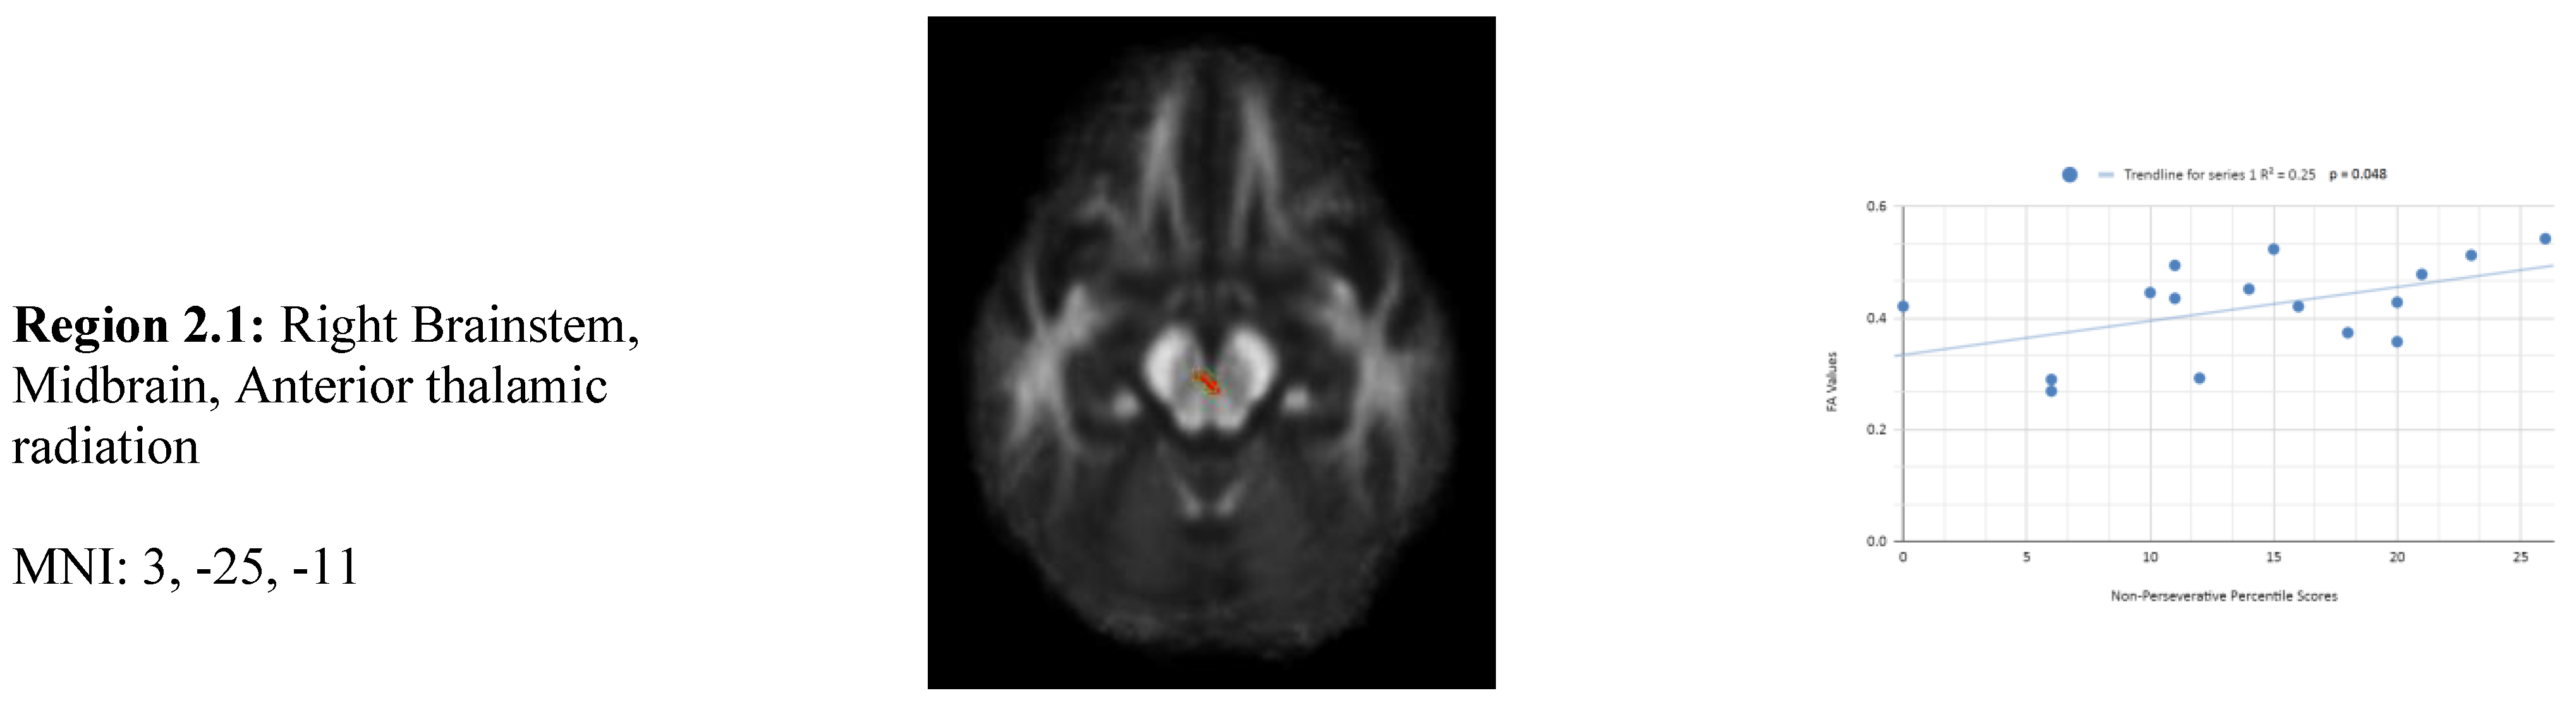

In addition, we also observed a statistically significant difference between the mean chronic mTBI patient WCST non-perseverative score of 16.67 ± and the normal mean standard WCST non-perseverative error score of 93.46 ± 15.02. A statistically significant positive linear correlation can be observed between reduced non-perseverative percentile scores and reduced FA in the right corpus callosum (CC), right anterior thalamic radiation (ATR), and right frontal pole (See Figure 2). Statistically significant negative linear correlations can be observed for the following regions: Middle Cerebellar Peduncle, Anterior corona radiata, Anterior limb of the internal capsule, Left Inferior longitudinal fasciculus, and Right Superior longitudinal fasciculus (Figure 2).

Figure 2 shows transaxial images of key brain regions of interest including the Anterior thalamic radiation (ATR), Corpus Callosum (CC), and Frontal Pole. These regions are correlated with reduced FA values and reduced non-perseverative response percentile scores in Excel to produce a scatterplot with the depicted correlations above. Reduced FA values are consistent indicators of TBI, and reduced non-perseverative percentile scores are associated with higher errors and poorer performance which is associated with cognitive impairment.

Contrary to the expected results, non-perseverative response percentile scores depict both positive and negative correlations, with 3 out of 9 correlations being positive correlations. The positive correlation is observed in the anterior thalamic radiation, corpus callosum, and frontal pole. The negative correlations are observed in the anterior corona radiata, superior longitudinal fasciculus, inferior longitudinal fasciculus, and Left Anterior limb of the internal capsule. The X-axis depicts the non-perseverative percentile scores (0-100 percentile) in each graph. The Y-axis displays FA values (0-1).

2 overall positive correlations were also observed between non-perseverative (Enp) percentile scores and FA values in the left and right frontotemporal and frontal-posterior regions derived from negative z-maps (0). These regions include regions 2.4 (Left Cerebellum, Posterior Lobe, Inferior Semi-Lunar Lobule, Middle cerebellar peduncle), 2.6 (Left Anterior limb of internal capsule), and 2.7 (Left Inferior longitudinal fasciculus) which were correlated together in the top left panel. Regions 2.5 (Right Anterior Cingulate, Anterior corona radiata), 2.8 (Right Superior longitudinal fasciculus), and 2.9 (Right Superior longitudinal fasciculus) displayed in the top right panel, were correlated together. When correlated individually, the regions express both positive and negative correlations in the non-perseverative correlations across all regions (Figure 2). However, when data points from multiple regions are correlated together in the FA scatterplot, positive correlations are observed. These overall positive correlations mean that as non-perseverative percentile scores decrease, so do FA values. DTI FA data is validated by WCST non-perseverative percentile scores.